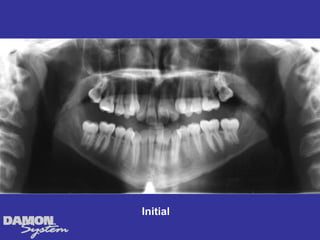

Treatment Planning โ€ข Ceph numbers โ€ข Model analysis โ€ข Pano X-rays โ€ข Facial analysis โ€ข Impact of growth/aging โ€ข Vestibular bone density โ€ข Tongue position/airway โ€ข How light a wire do I need to stimulate blood flow?

Why is theupper so crowded? Initial โ€“ Tongue position?